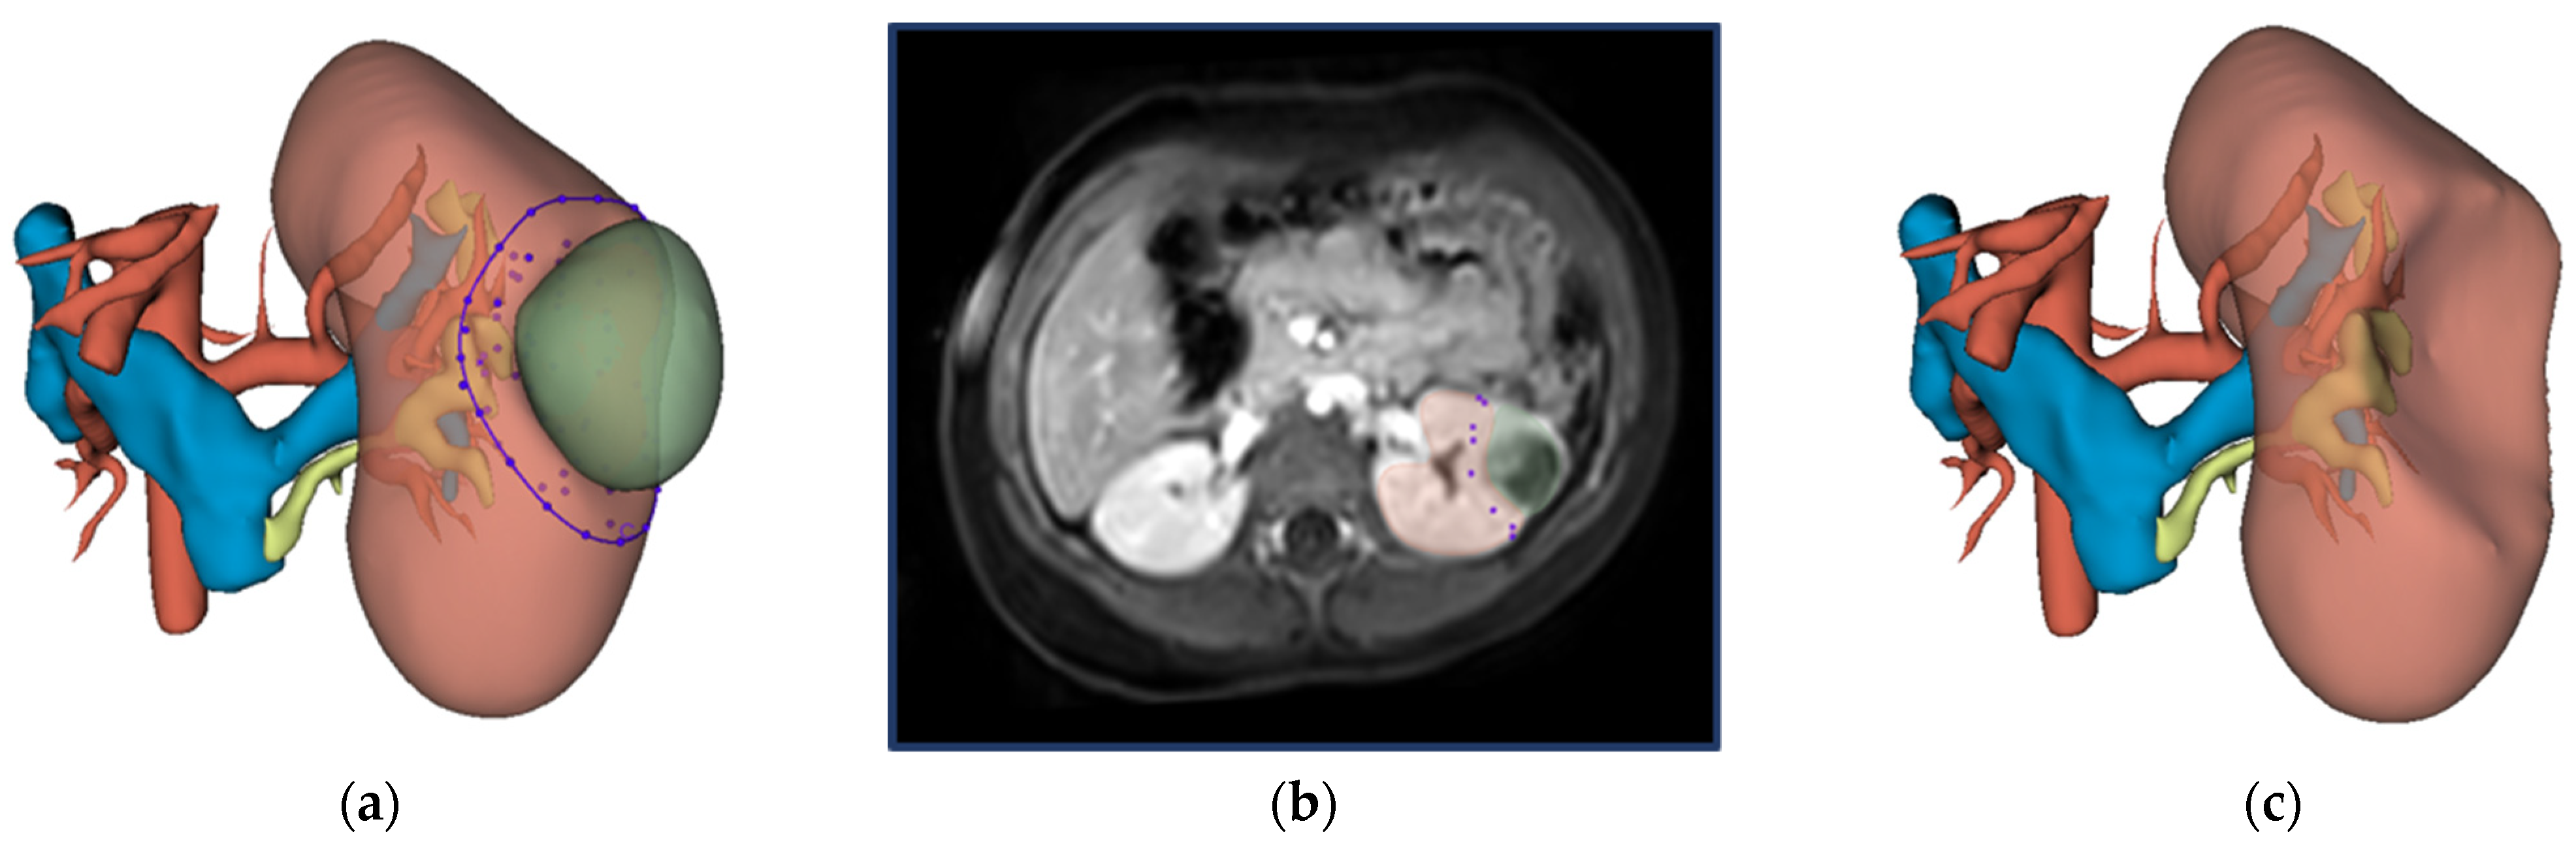

2.3. Virtual Resection